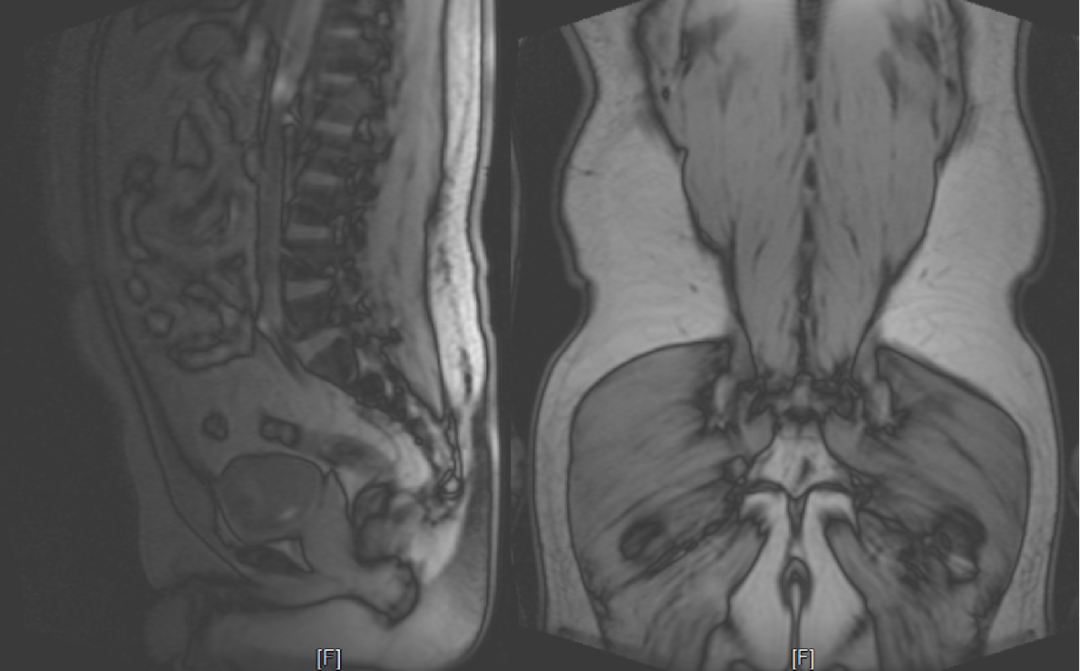

男,32 岁,腰背部疼痛一个月。

发现 L4-5、L5-S1 水平马尾神经位置前移、明显聚拢,马尾神经间脑脊液间隙明显变小。

回过头再看第二个病例,发现椎管内背侧硬膜外脂肪增多,超过椎板前缘,向前推挤马尾神经,使其明显聚拢

回头看第二个病例皮下和内脏脂肪沉积

回头看第二个病例同样存在深层脂肪的水肿